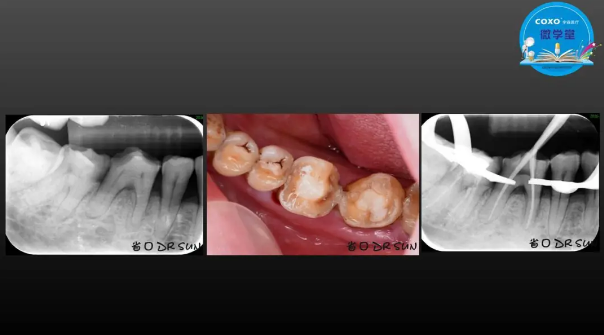

主任醫(yī)師,牙體牙髓副主任, 廣東省口腔醫(yī)院牙體牙髓科 主任醫(yī)師。2003年碩士研究生畢業(yè),研究方向?yàn)檠荔w牙髓病學(xué),擅長(zhǎng)于牙體牙髓病的診斷、齲齒、牙髓炎、根尖周病的治療以及前牙美容修復(fù)。